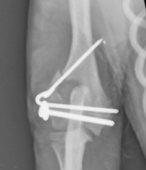

橈尺骨骨折

プレートスクリュー固定

治療には多くの整形疾患で手術が必要になります。術式は折れ方や場所、脱臼の場所などにより様々で、多様な方法を組み合わせて行います。

手術器具は、整形用ドリル(骨を切ったり、スクリュー(ネジ)用の穴を開けたりします)、整形用ラウンドバー(骨を削る器具です)、各種骨プレート・スクリュー、ワイヤー、ロッキングプレート・ロッキングスクリュー(通常のプレートより強固な固定が可能です)、骨セメント、整形器具を揃えており、幅広い手術に対応可能です。